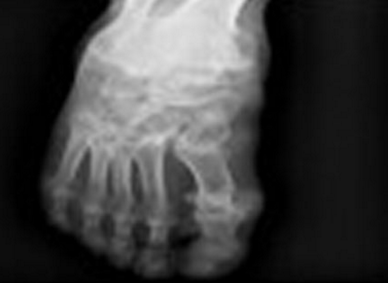

高尿酸血癥是指370C時血清中尿酸含量男性超過416μmol/L (7.0mg/dl);女性超過357μmol/L(6.0mg/dl)。高尿酸血癥患者,如果沒有治療5年后12%可出現(xiàn)痛風(fēng)石,20年后出現(xiàn)痛風(fēng)石的比例為55%。血尿酸降至正常可減少關(guān)節(jié)炎發(fā)作。